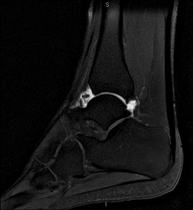

Exploració per estudiar aquesta articulació i les lesions freqüents de lligaments (esquinços), així com l'afectació d'altres estructures, com el cartílag o l'os. També és de gran utilitat per diagnosticar alteracions al tendó d'Aquil·les (tendinitis o trencaments). La durada aproximada és de 20 minuts. No utilitza radiació ionitzant. - RM de Peu

Exploració per a l'estudi de les lesions en petites estructures anatòmiques de l'articulació que solen produir-se en pacients que pateixen luxació o inestabilitat crònica. L'estudi ve precedit per una injecció de contrast a l'interior de l'articulació, realitzada sota control de raigs X. La durada total dels dos procediments és de 50 minuts.